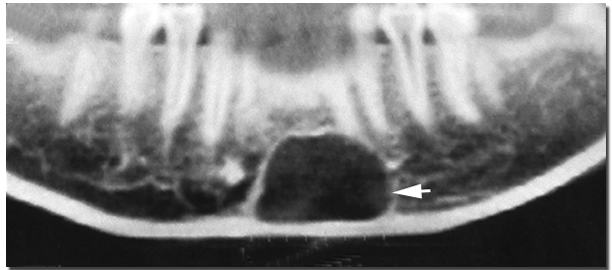

静止性骨囊肿(static bone cyst)实际上是发生于下颌骨后份舌侧的解剖切迹,它是由于发育过程中,涎腺和其它软组织的增殖或迷入而引起的下颌骨局限性缺损。X线片上可表现为囊肿样透射区。有时还可双侧同时发生。这型假性囊肿一般无症状,多在X线检查时偶然发现。好发于下颌磨牙及下颌角区,多位于下齿槽神经管的下方,X线表现为边缘致密的卵圆形透射区。组织学观察,骨缺损区不存在明显的囊肿,可见到涎腺组织、脂肪组织、纤维结缔组织和肌肉等。